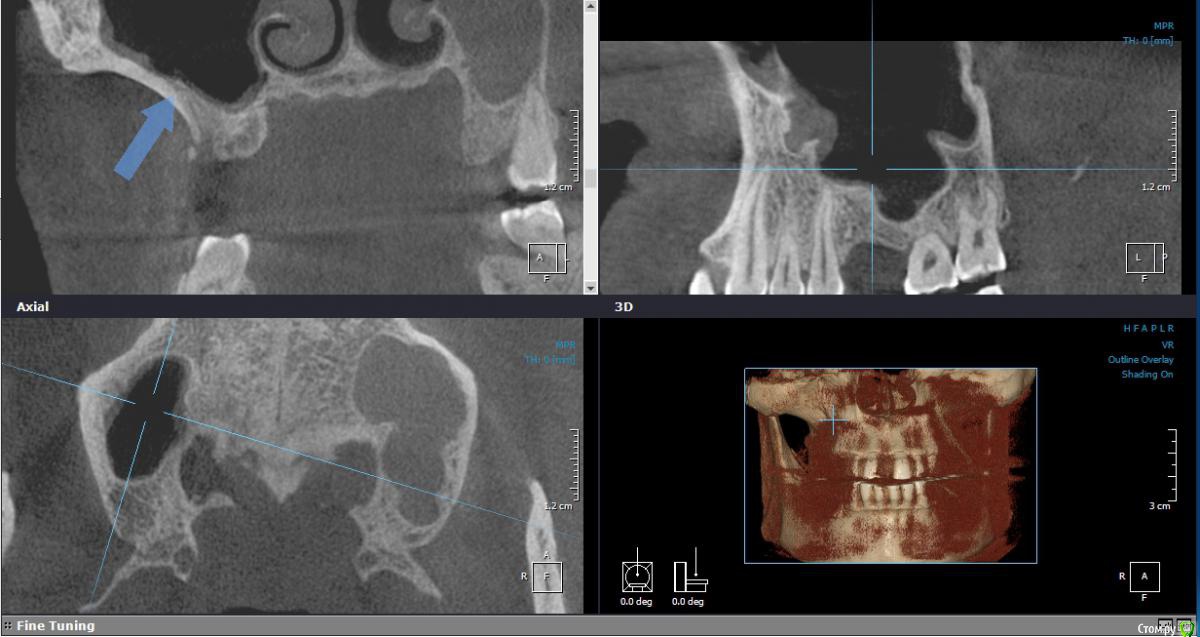

Iv_serg Опубликовано 6 сентября, 2017 Поделиться Опубликовано 6 сентября, 2017 Коллеги, планирую ОСЛ с имплантацией. На КЛКТ обнаружил вот такую толщину наружней стенки синуса. Часто ли у вас такое бывает и чего стоит опасаться? Ссылка на комментарий

Iv_serg Опубликовано 6 сентября, 2017 Автор Поделиться Опубликовано 6 сентября, 2017 Срез Ссылка на комментарий